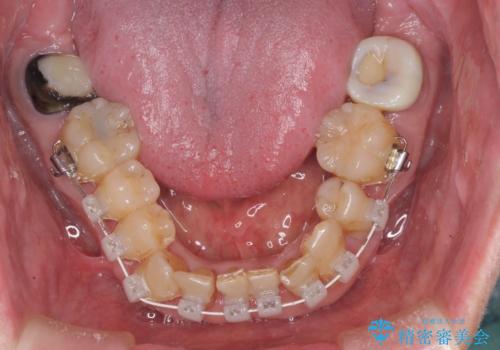

また、前歯の部分矯正も希望されたため、歯周外科処置と平行して矯正治療を行うこととしました。

患者様ご自身が痛みには強いとおっしゃっていたので、治療中は特に辛いと感じることはなく進めることができました。

気になっていた歯の痛みや歯肉からの出血がなくなり、改善したいと思っていた外見も綺麗に仕上がり、大変満足していただきました。